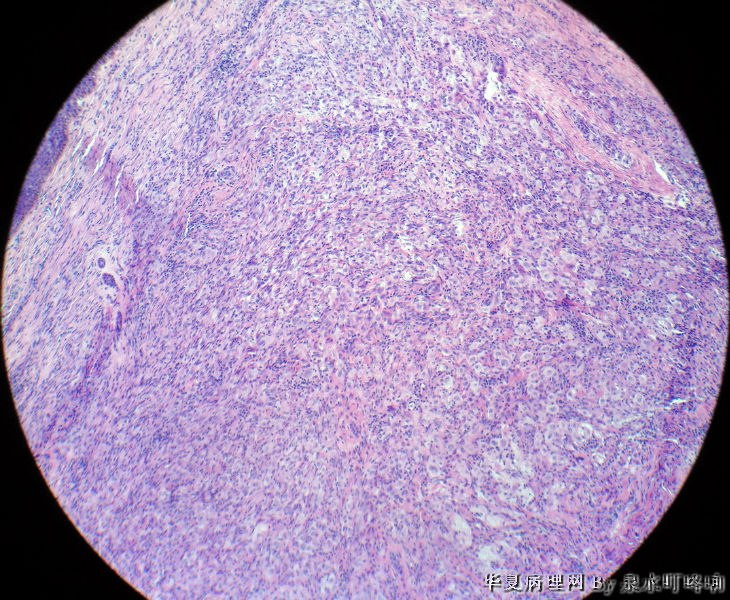

• 颈后部肿物图2

图2

肿瘤较小,梭形细胞间质内可见一些较大细胞,核小,胞质丰富,可见胞质内较多颗粒,考虑颗粒细胞瘤,做免疫组化标记S-100证实。

病理改变中浸润的细胞考虑组织细胞来源。诊断考虑单发性网织细胞肉芽肿(网织组织细胞瘤)可能。如考虑Rosai-Dorfman病,病理改变中没有明显淋巴细胞浸润和吞噬现象,需要免疫组化来明确诊断。

北京肿瘤医院会诊:纤维组织细胞瘤。